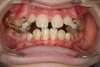

La gouttière orthopédique et le masque facial sont utilisés dans les malocclusions de classe III : dents et mâchoire supérieure trop en arrière, dents et mâchoire inférieure trop en avant).

On parle de prognathisme mandibulaire et/ou de brachygnathie maxillaire.

Cette dysmorphose dento-squelettique est une anomalie osseuse préoccupante car elle s’aggrave au cours de la croissance de l'enfant.